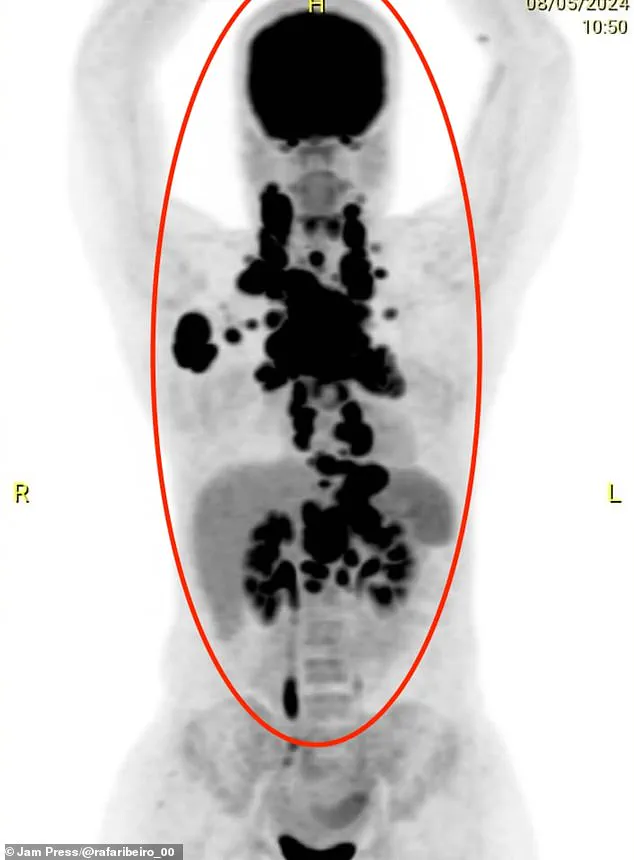

Initially, doctors misdiagnosed her condition as pneumonia or an allergic reaction, but when she collapsed and could no longer eat, scans revealed the grim truth: her upper body was packed with tumours, each one a silent aggressor against her life.

Days later, the tumours had grown so aggressively that they compressed her oesophagus, making it impossible to swallow solid food. 'The tumours were crushing me from the inside.

My oesophagus was compressed, and my heart felt like it was being taken over, but it was just the pressure from the tumours,' she said.